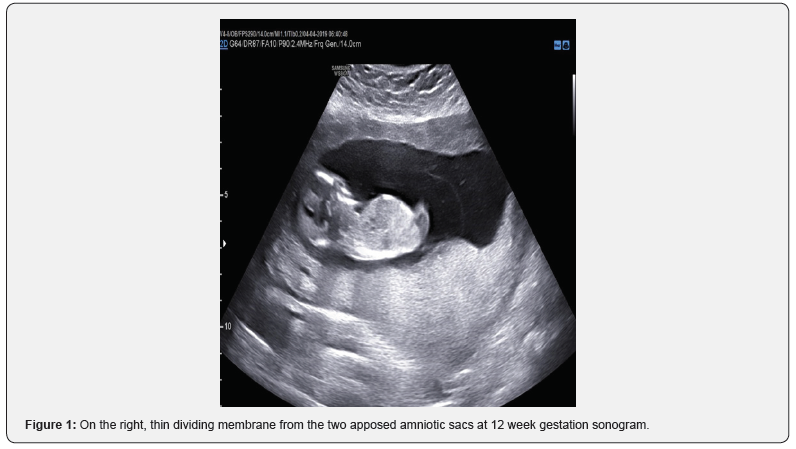

We present a case of a 40-year-old patient (G3, P2) admitted at our Department, presented with a spontaneous twin pregnancy. Prenatal monitoring with ultrasound examination confirmed a monochorionic twin pregnancy (Figure 1). Ultra sonographic follow up was settled every 2 weeks, in order to diagnose potential MCDA complications (Monochorionic Diamniotic Twins). Ultra sonographic evaluation during 14th week of gestation confirmed the existence of the diving membrane, sign of Monochorionic-Diamniotic pregnancies (Figure 2).